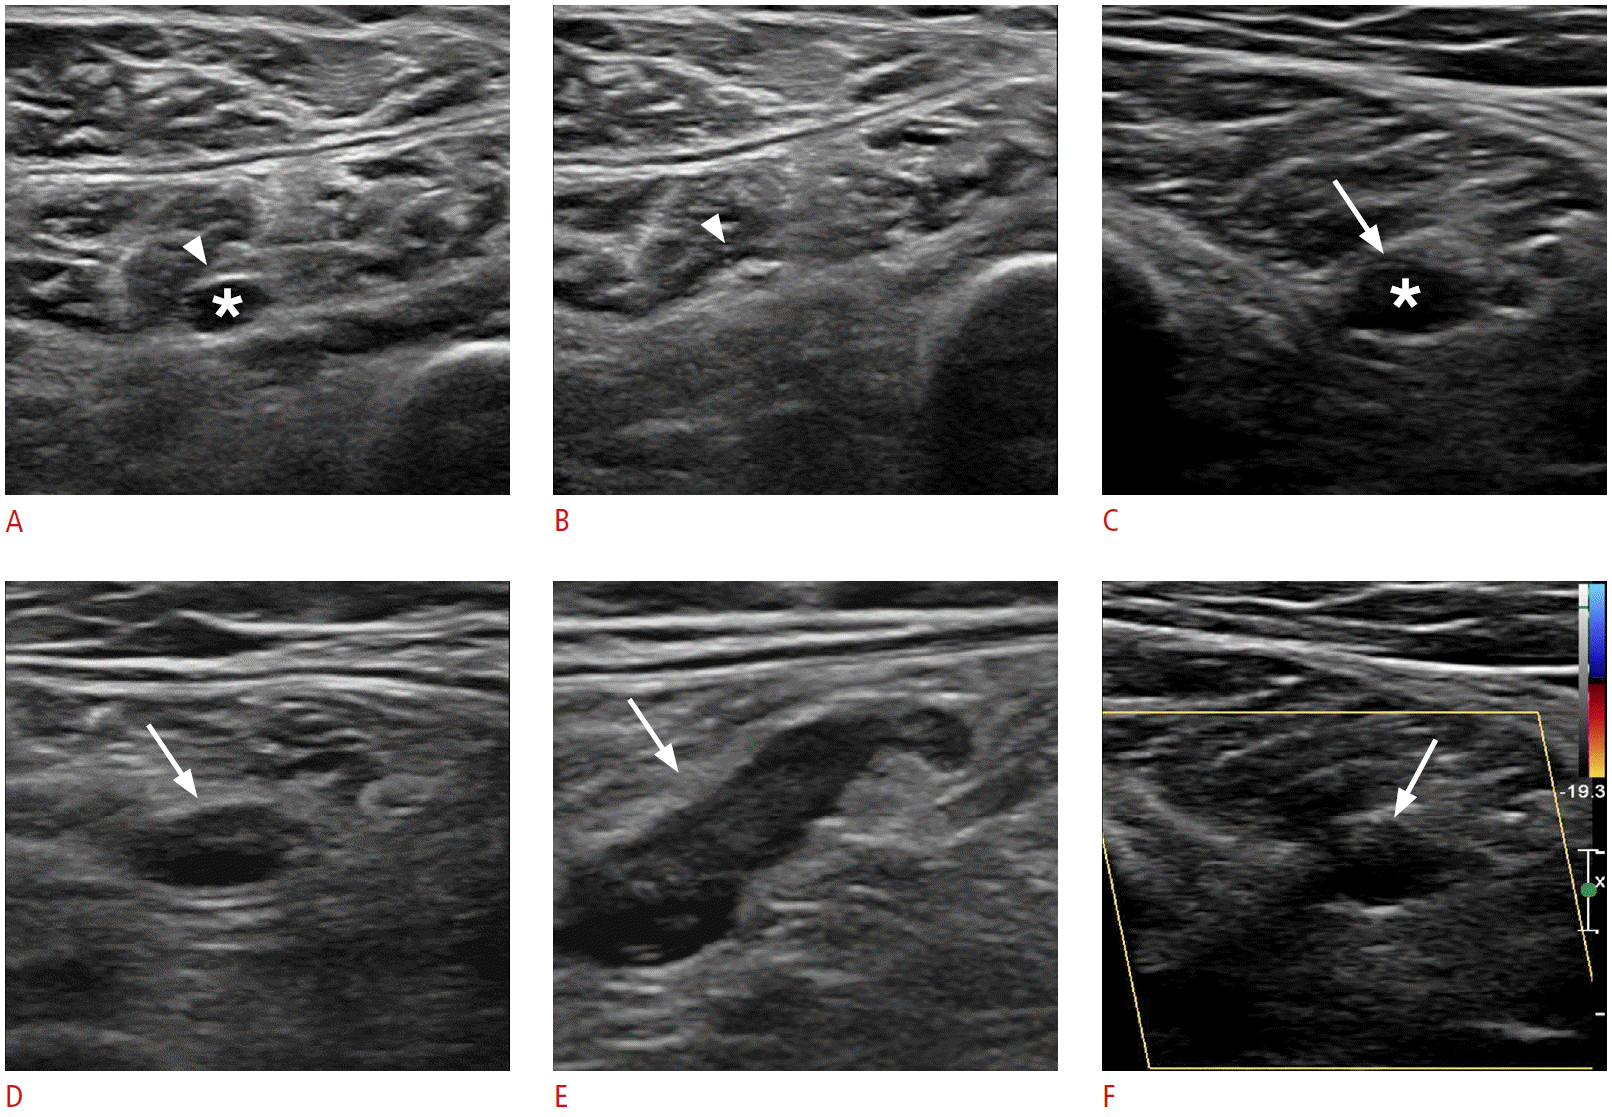

Fig. 2.

Normal findings versus acute deep vein thrombosis in the soleal vein.

A, B. Non-compressed (A) and compressed (B) gray-scale axial gray-scale ultrasonography shows an anechoic soleal vein (asterisk), which is collapsed on compression (arrowhead), indicating no evidence of deep vein thrombosis. C-F. Non-compressed (C) and compressed axial and long-axis gray-scale (D, E) and color Doppler (F) images show the typical ultrasonographic findings of soleal intramuscular thrombus (arrows).